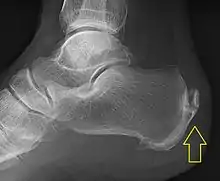

.jpg.webp)

Achilles tendinitis is usually diagnosed from a medical history, and physical examination of the tendon. Projectional radiography shows calcification deposits within the tendon at its calcaneal insertion in approximately 60 percent of cases.[16] Magnetic resonance imaging (MRI) can determine the extent of tendon degeneration, and may show differential diagnoses such as bursitis.[16]